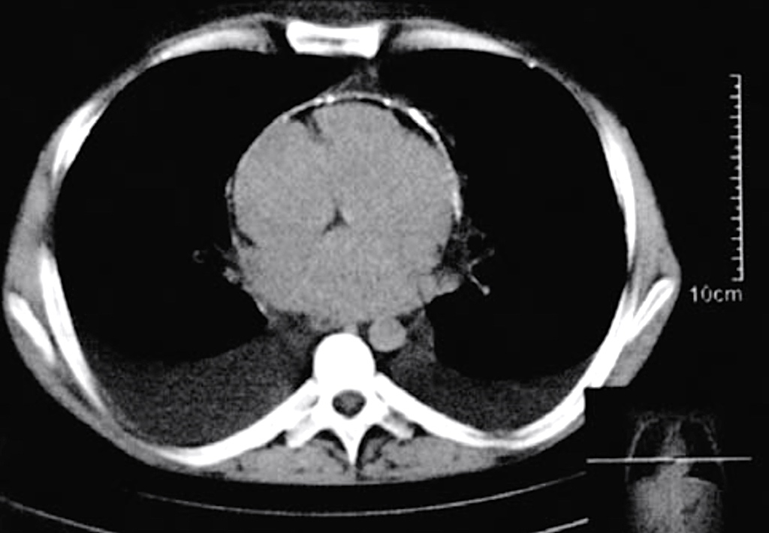

2. Компьютерная томография

Листки перикарда, эпикардиальный жир, жидкость и образования в полости перикарда и его кальциноз очень хорошо видны при КТ. Даже на КТ органов грудной полости без внутривенного контрастирования камер сердца и сосудов вышеописанные изменения перикарда хорошо видны. КТ дает возможность очень точно оценить объем интраперикардиальной жидкости (на основании суммации ее объемов на срезах), измерить толщину листков перикарда во всех его отделах, измерить (в том числе количественно) степень кальциноза. Однако на сегодняшний день при направлении пациента с перикардитом на КТ, рекомендуется выполнять КТ сердца с кардиосинхронизацией и внутривенным контрастированием камер сердца и сосудов в артериальную фазу (A06.10.009.001). В этом случае получаются изображения сердца, перикарда и средостения с высоким качеством. Возможно создание многоплоскостных и объемных трехмерных реконструкций. КТ сердца при заболеваниях перикарда может быть выполнена на всех современных КТ любого класса (начиная от систем с 16 рядами детекторов и выше), имеющих опцию синхронизации с ЭКГ.

Благодаря высокой разрешающей способности, позволяющей выявлять утолщение листков перикарда от 2 мм (что примерно в 2 раза больше толщины неизмененного перикарда), КТ используется для диагностики констриктивного перикардита с кальцификацией или без нее [1].

Особенностями КТ-картины, позволяющей отличить утолщение листков перикарда от перикардиального выпота являются: наличие очагов пониженной плотности, типичное утолщение передней стенки перикарда, отсутствие изменений в положении больного лежа и усиление сигнала при введении контрастного вещества. Однако при небольшом количестве жидкости КТ не всегда способна выявить это различие, в отличие от МРТ.

Высокая разрешающая способность КТ играет важную роль в дифференциальной диагностике констриктивного перикардита и рестриктивной кардиомиопатии. Выявляемое утолщение париетального листка перикарда в среднем от 4 до 20 мм позволяет разграничить эти состояния [153]. Однако у 28% (18% при аутопсии) больных с констриктивным перикардитом не определяется утолщение перикарда [154].

Кальцификация перикарда, выраженная в той или иной степени, визуализируется у 50% пациентов. При этом КТ позволяет, в отличие от ЭхоКГ, визуализировать отложение кальция на любой поверхности сердца, особенно в местах с большим содержанием эпикардиального жира (атриовентрикулярные борозды и основание сердца) (Приложение А3, рис. А3-10) [154, 155].

Косвенными признаками констриктивного перикардита будут: уменьшение и циркулярная деформация правого и левого желудочков. Нарушение диастолической функции правого желудочка проявляется расширением нижней полой и печеночных вен, гепатоспленомегалией, асцитом и плевральным выпотом.